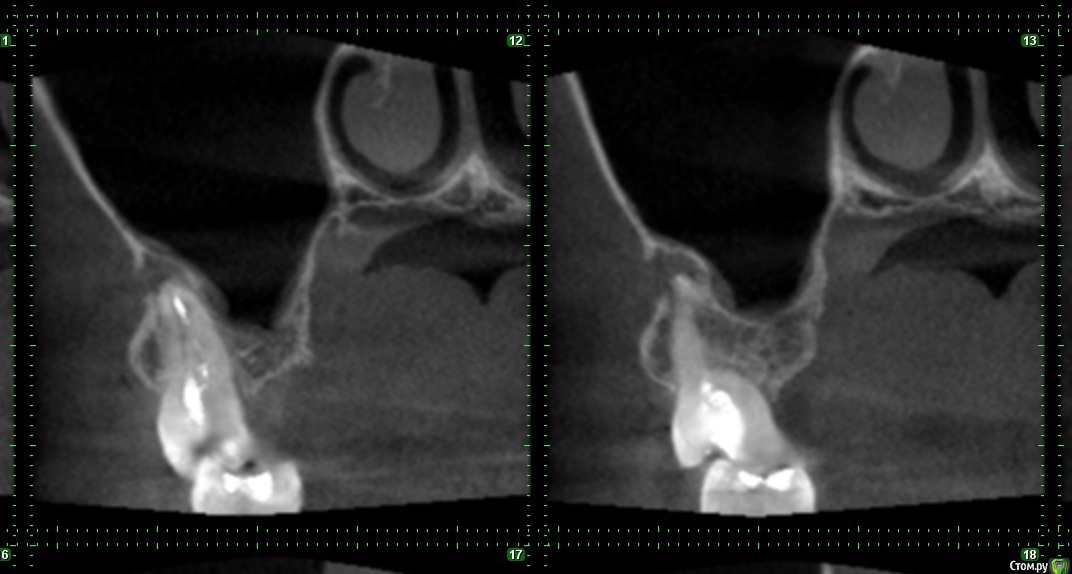

Seven Опубликовано 4 февраля, 2019 Поделиться Опубликовано 4 февраля, 2019 ЗдравствуйтеЗуб на верхней челюсти, справа, перед зубом мудрости.Зуб, лечился с удалением нервов лет 5 назад. Сейчас на протяжении пару месяцев чувствовалось распирание и жжение, перед этим между ним и зубом мудрости часто попадала пища и я чувствовал болезненность.фото, оно большое https://b.radikal.ru/b42/1902/18/ad6fa98f7463.jpgДве недели назад пошел к зубному. Определили на корне этого зуба кисту фото 12,13 в зеленой рамке, 8 в красной. Врач прочистила канал и заложила лекарство, под временную пломбу. Прочистка пошла не совсем по плану, инструмент пошел по красной линии на рисунке(по мотивам того что я видел на ренгене), врач сказала раз крови нет значит в кость не попали. Да под зубом есть уплотнение на десне, до введение лекарства было довольно болезненное, теперь намного меньше. Собственно теперь проблемы, прошло две недели, и две недели этот зуб у меня болит, причем собственно сам зуб не очень, болит чуть выше него, от ноющей до очень сильной боли, вместе с ним болит голова, и глаза, отдает немного в ухо. Сильная боль радует меня по ночам и утрам. По совету врача пью Нимесил, помогает, но без него продолжает болеть. Так и должно быть ? или что то идет не так ? Врач неделю назад на приеме говорила надо наблюдать, но т.к. он меня очень беспокоит решил дополнительно спросить у Вас. Насколько вероятно развитие осложнений в моей ситуации, если время пользуясь обезбаливающими побегать по другим врачам ? Или бежать вырывать ? Если вырывать то случай простой, или искать врача поопытнее/подороже ? Начитался интернетов, что у меня корень зуба в гайморовой пазухе, может быть осложнение =) да и киста. Ссылка на комментарий